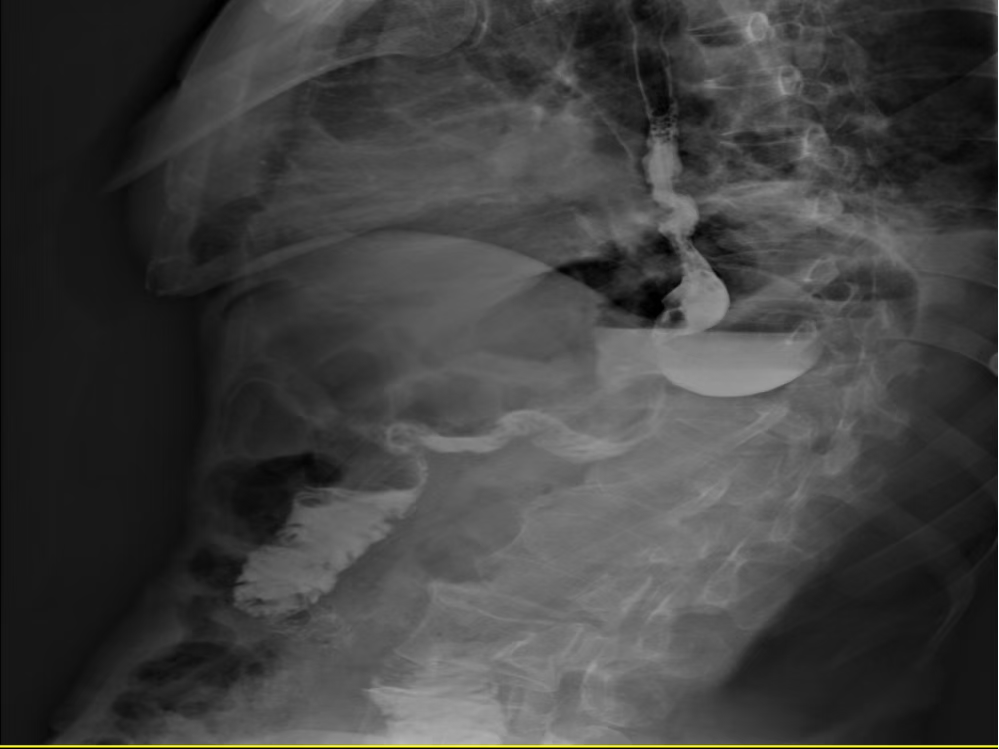

•POD4: A gastrointestinal contrast study confirmed smooth contrast passage through the distal gastrectomy anastomosis with no abnormalities. The abdominal drainage tube was removed, and he was advised to gradually increase food intake, supplemented with short-peptide enteral nutrition powder.

On post-operative day 4, a gastrointestinal contrast study revealed: following distal gastrectomy, contrast passage through the anastomosis was smooth, with no abnormalities detected.